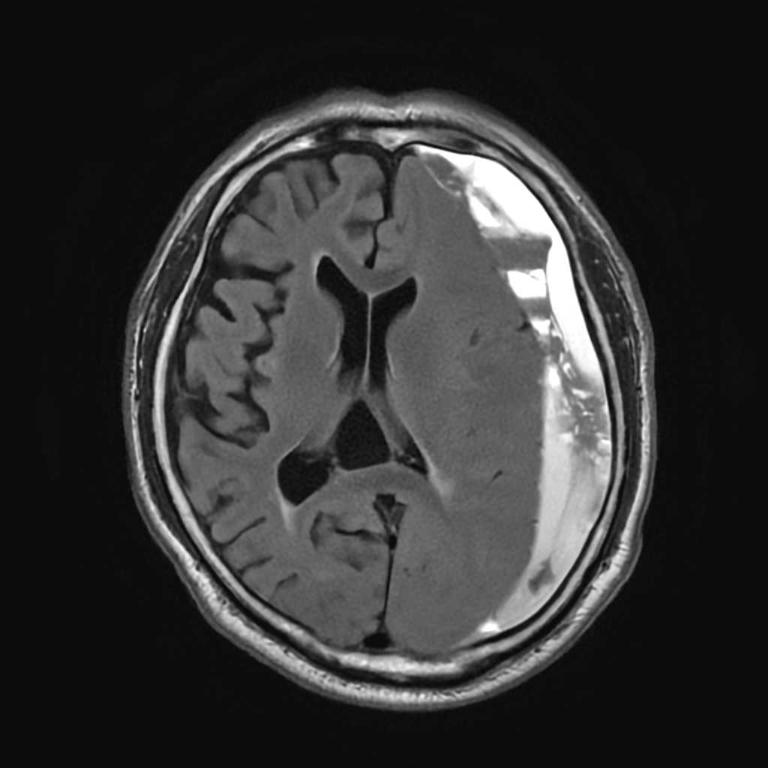

頭部

硬膜下血腫